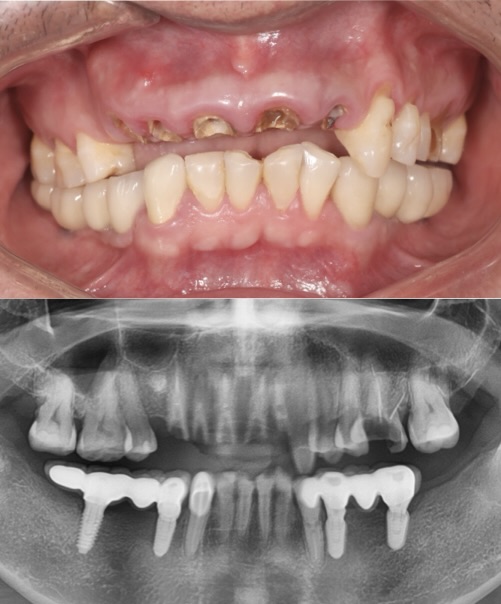

Before

After

IMMDEDIETE IMPLANT -MULTIPLE

This patient presented with severely damaged anterior teeth. Treatment involved immediate implant placement paired with bone grafting to restore lost support and preserve the soft tissue profile.

The case was completed with a final fixed prosthesis, offering a beautiful, functional, and long-lasting result. Expertly restored at Moral Dental Clinic.